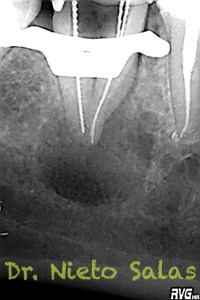

Nos remiten a la clínica a una paciente con un tratamiento previo de endodóncia realizado ya hace unos 5 años y que presenta una agudización del proceso. Se trata de un fracaso endodoncico por una falta de sellado tanto coronal como apical, en el que en el espacio intra-conductos nos encontramos dos léntulos, y en el acceso a los mismos un perno prefabricado.

Los puntos fuertes serán la retirado del perno y de los léntulos, a priori, no muy complicado, pero todo puede cambiar dentro de los conductos. Nuestro objetivo en la primera sesión será llegar a determinar la longitud de trabajo de los diferentes conductos, conformarlos y colocar nuestro Hidróxido de Calcio.

Presentaba un sistema de conductos en el que el conducto distal era acintado y los mesiales podían unirse después de instrumentarlos.

Me gusta ser conservador con los diámetros apicales, para deformarlos lo menos posible. En este caso no fue así por la anatomía que presentaba, adapté bien los conos maestros con un diámetro más o menos 45 en el conducto distal(recuerda que era acintado con lo que no es posible un único cono apical) y 30 los mesiales.